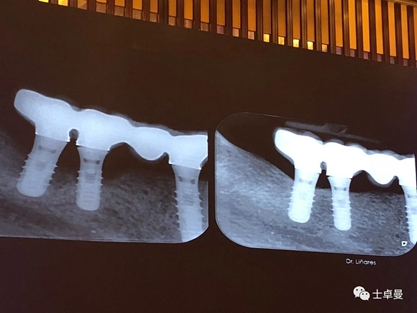

種植體周圍炎是影響牙種植遠(yuǎn)期效果導(dǎo)致種植失敗的主要原因之一。和天然牙一樣,如果口腔衛(wèi)生不良,菌斑滯留,那么細(xì)菌微生物就會對種植體周圍的軟組織不斷刺激,使機(jī)體產(chǎn)生炎癥反應(yīng),表現(xiàn)為黏膜的紅腫、探診出血甚至溢膿。也可通過X片來評估種植體周圍的骨量情況。

手術(shù)方式治療則需通過翻瓣清潔種植體及修復(fù)體上菌斑牙石,推薦在此過程中使用士卓曼鈦刷,因?yàn)樵撯佀⒉粫p傷種植體表面細(xì)微結(jié)構(gòu)。之后進(jìn)行植骨蓋膜來促進(jìn)種植體周圍吸收部分的骨的重建。